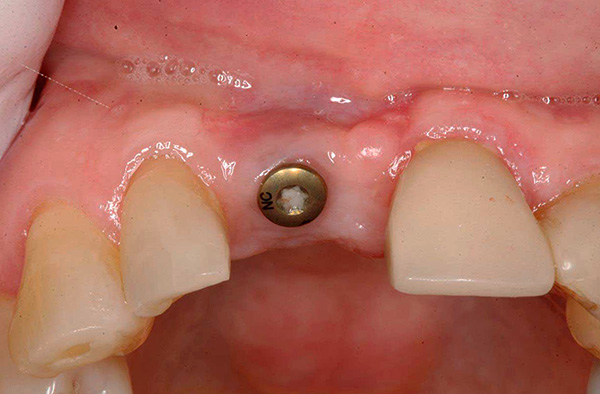

- Dopo l'attecchimento dell'impianto riuscito - ripetuto incisione gengivalecoprendo il moncone sull'impianto, rimuovendo il moncone e fissando il moncone di guarigione (eseguito 2-3 settimane prima dell'installazione di una protesi permanente). La prima gengiva consente di regolare la posizione della mucosa molle attorno alla futura corona;

- Rimozione del precedente gengivale e sostituzione con un moncone (un elemento che funge da base per la protesi), installandolo sul moncone e inserendo una protesi permanente realizzata prima delle calotte.